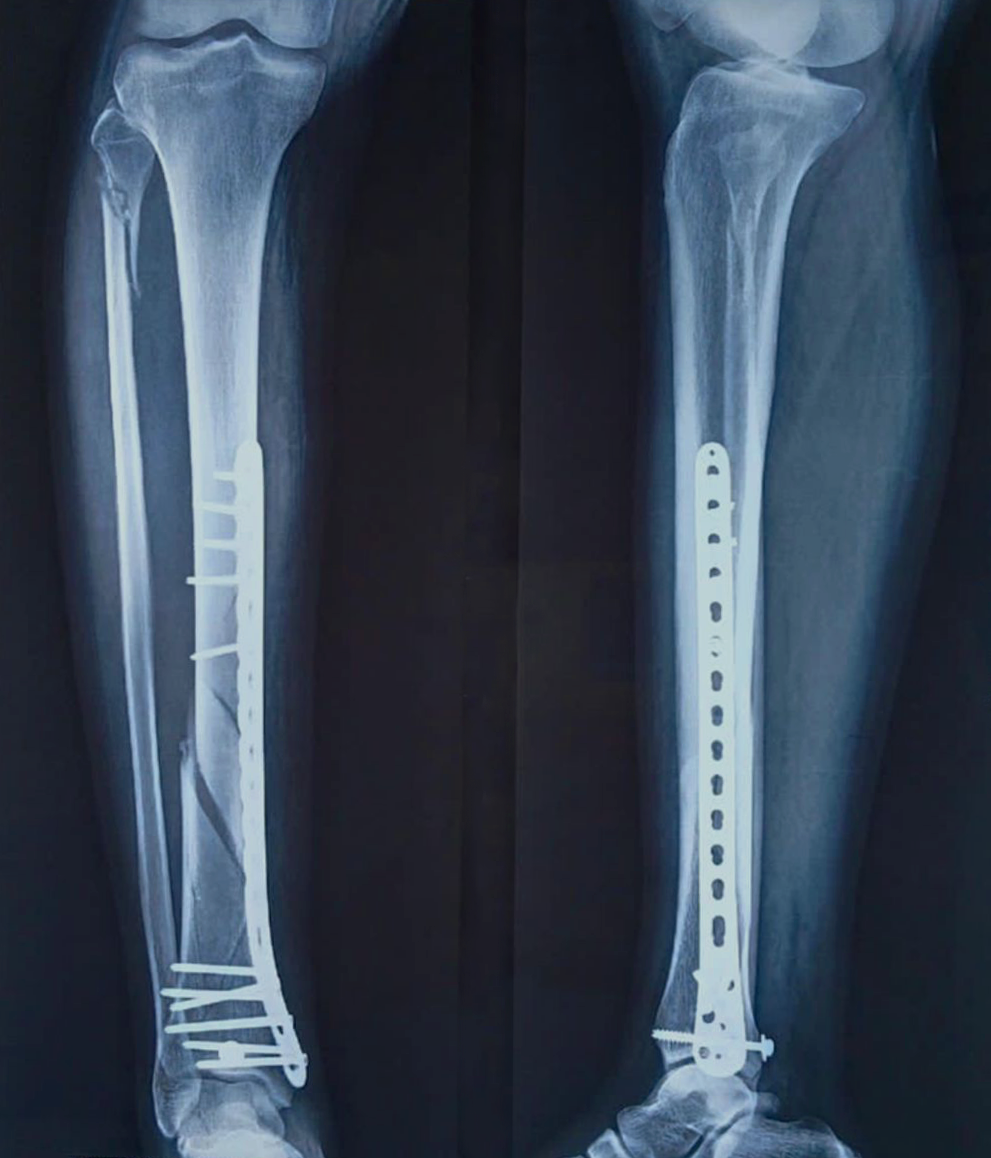

- Fracture Treatment: We specialize in the surgical and non-surgical treatment of

fractures, utilizing advanced techniques to ensure optimal healing and recovery.

- Expertise in Trauma Care: Dr. Zambare is highly skilled in managing complex trauma

cases, including multi-limb injuries and severe fractures. His expertise ensures that patients receive

precise and effective treatment for their injuries.